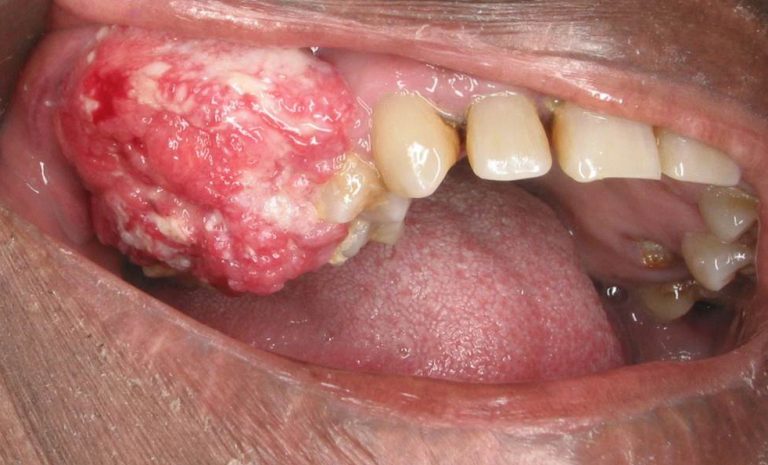

Kanser mulut merupakan ketumbuhan tisu yang tidak normal di dalam mulut. Pengesanan dan rawatan awal dapat mencegah berlakunya hilang upaya yang teruk dan dapat meningkatkan kualiti kehidupan pesakit. Di Malaysia, ia merupakan kanser yang ke-21 kerap terjadi manakala ia berada di tangga ke-8 di dunia.

Apakah tanda-tanda kanser mulut ?:

• Ulser yang lambat atau tidak sembuh

• Tompok putih (leukoplakia)

• Tompok merah (erythroplakia)